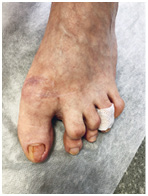

Хирург не заботится об эстетической стороне вопроса. Ему важно решить проблему, чтобы вы больше не испытывали дискомфорт. Часто после хирургического лечения ноготь меняет форму, становится менее красивым – к этому нужно быть готовым.

Иллюстрация к книге — Подология понятно. Важен каждый шаг. Справочник по проблемам подологии для клиентов и мастеров эстетики [i_269.jpg]

Иллюстрация к книге — Подология понятно. Важен каждый шаг. Справочник по проблемам подологии для клиентов и мастеров эстетики [i_270.jpg]

Иллюстрация к книге — Подология понятно. Важен каждый шаг. Справочник по проблемам подологии для клиентов и мастеров эстетики [i_271.jpg]

Иллюстрация к книге — Подология понятно. Важен каждый шаг. Справочник по проблемам подологии для клиентов и мастеров эстетики [i_272.jpg]

Результат работы за 5 месяцев: подолог использовал крючковые коррекционные системы, а хирург сделал пластику внутреннего бокового валика (из-за хронических воспалений боковой валик стал гипертрофированным и давил на ноготь, от чего клиент испытывал постоянный дискомфорт)